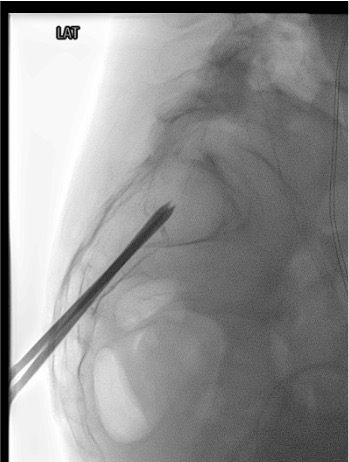

- Fluoroscopy suite (biplanar preferred: AP + lateral simultaneously) OR CT fluoroscopy

Biplanar Fluoroscopic or CT Confirmation of Trocar Position

PMMA Cement Injection

- Long-axis (caudo-cephalic): standard preferred approach; needle inserted in cauda-to-cephalad direction along Zone I alar axis; allows complete fracture line filling; developed by Smith & Dix 2006